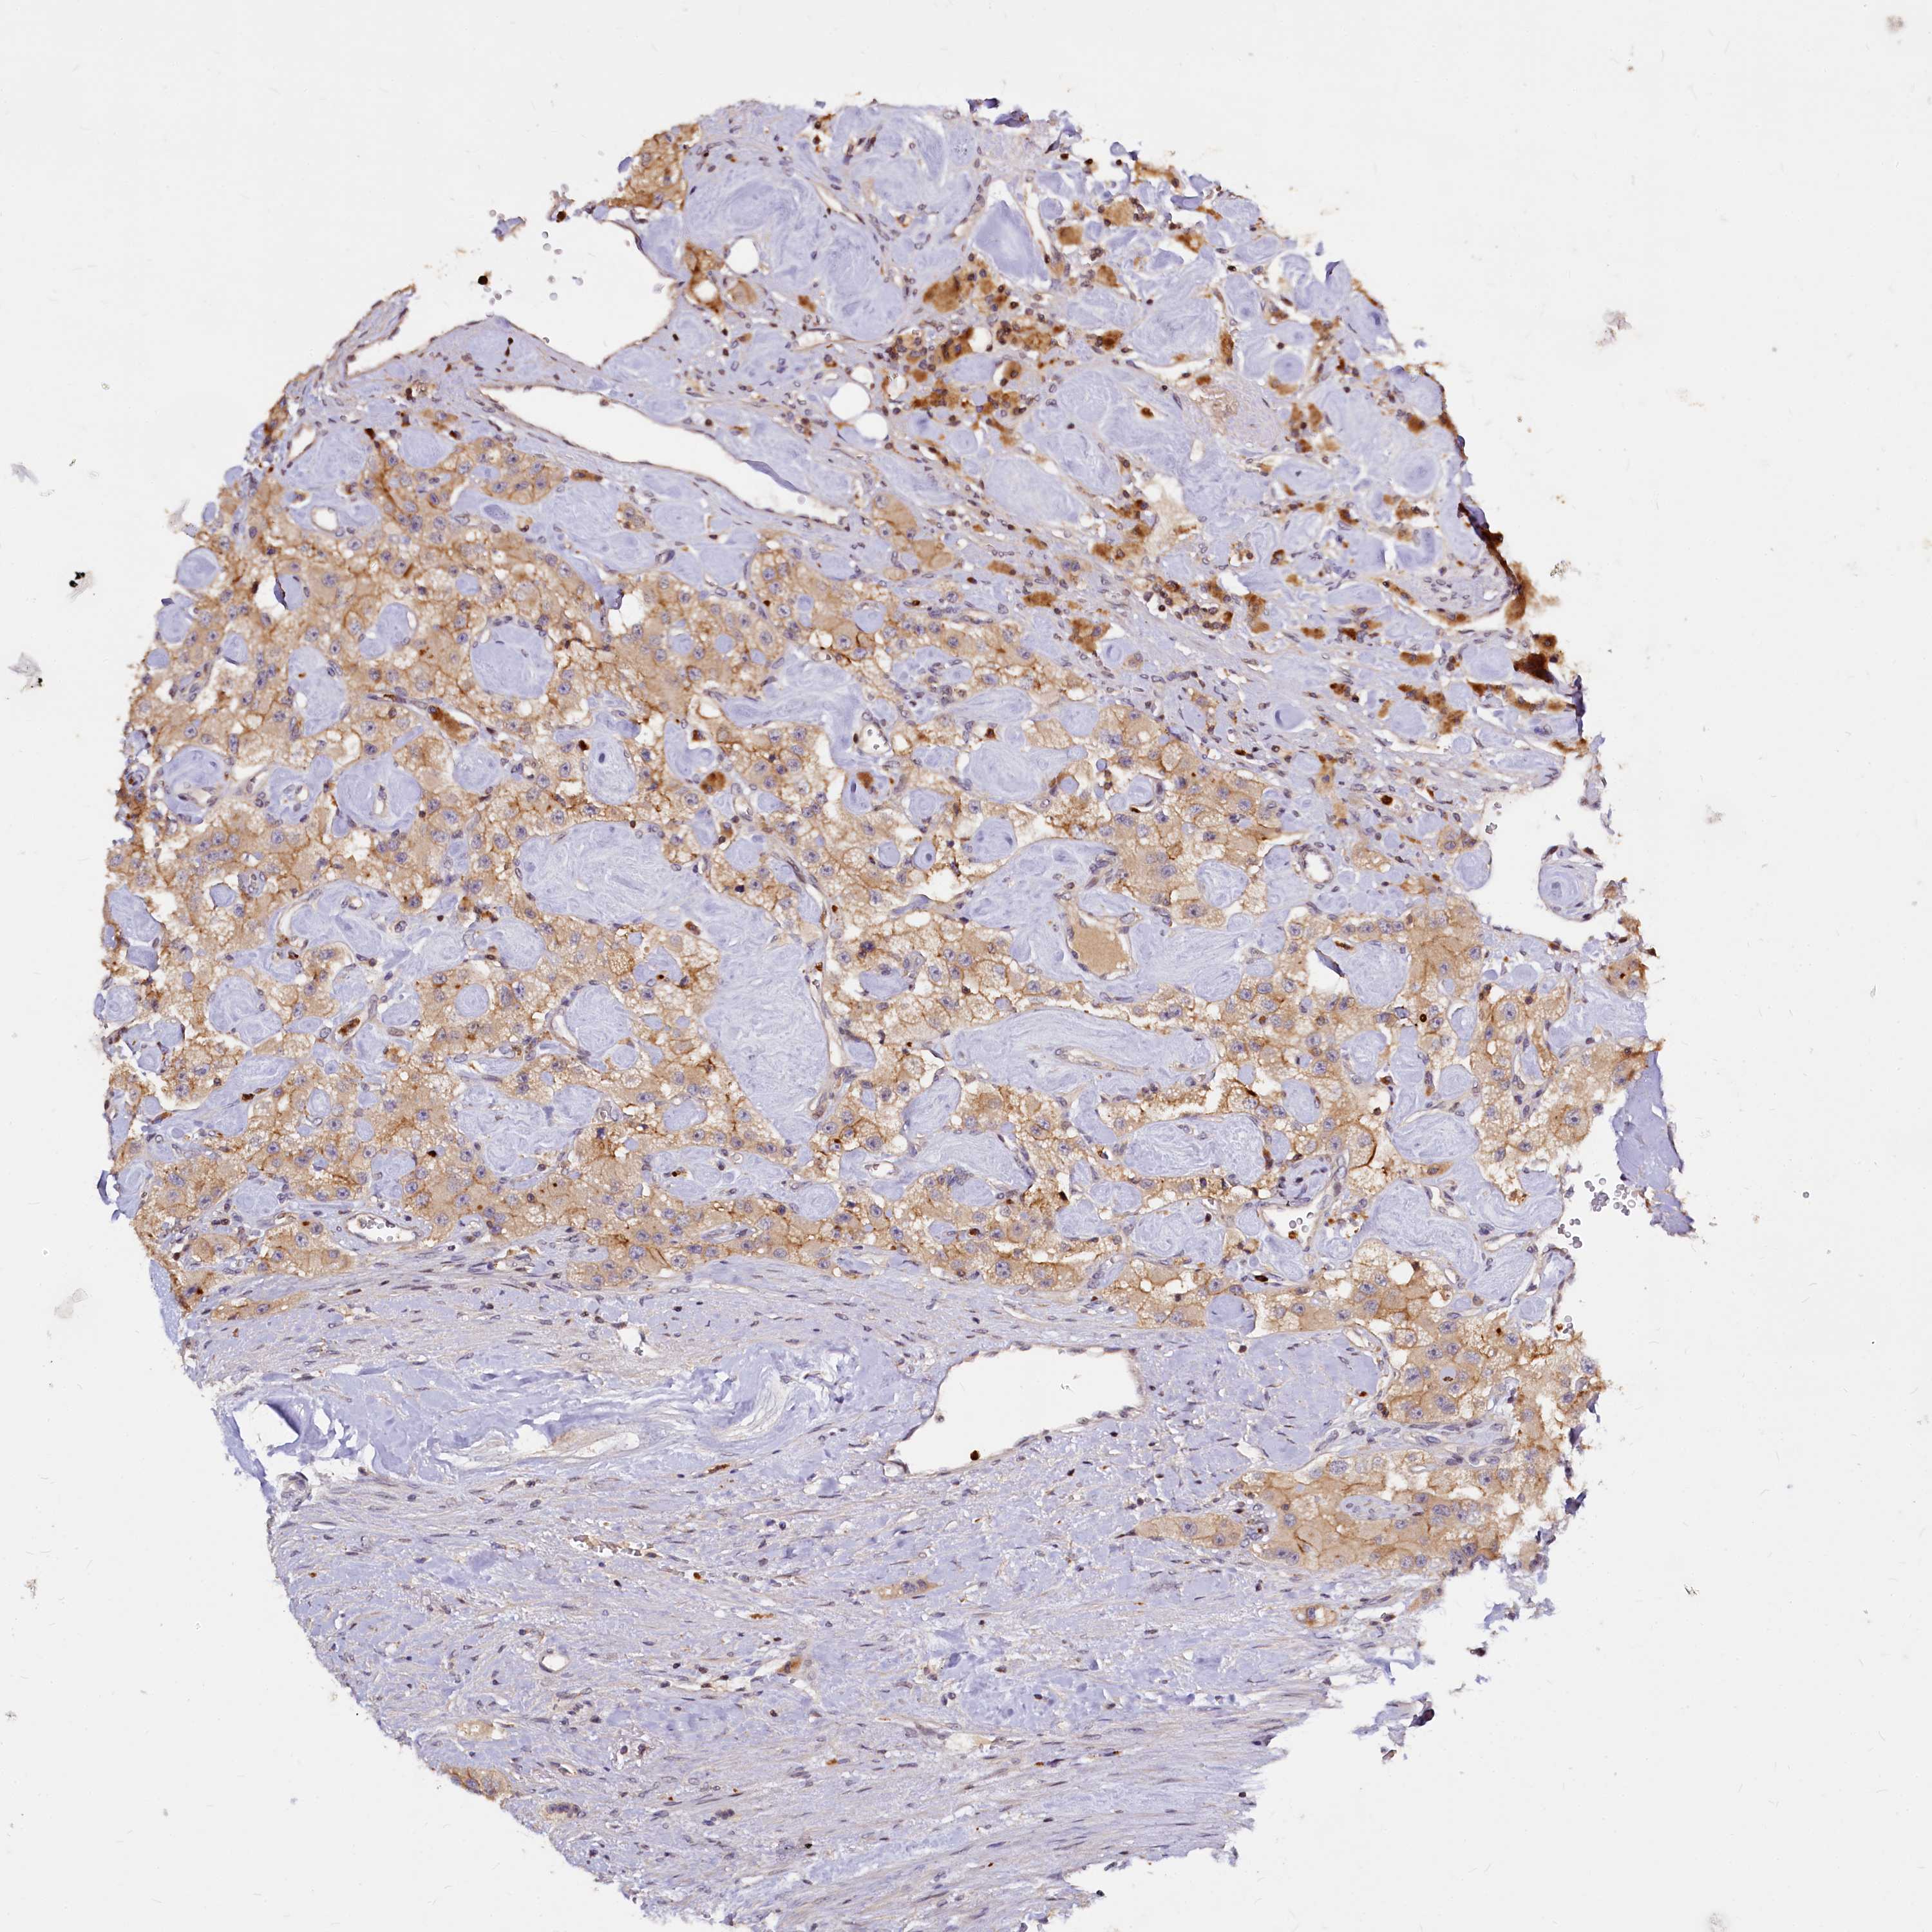

CARCINOID - Protein expressioni

A mouse-over function shows sample information and annotation data. Click on an image to view it in a full screen mode. Samples can be filtered based on level of antibody staining by selecting one or several of the following categories: high, medium, low and not detected. The assay and annotation is described here.

Each image is clickable and will lead to virtual microscopy that enables deeper exploration of all samples and also displays staining intensity scores, fraction scores and subcellular localization as well as patient and tissue information for each sample.

Antibody HPA039904

Staining

High

Medium

Low

Not detected

Intensity

Strong

Moderate

Weak

Negative

Quantity

>75%

75%-25%

<25%

None

Location

Nuclear

Cytoplasmic/membranous

Cytoplasmic/membranous,nuclear

Carcinoid, malignant, NOS

Carcinoma, NOS